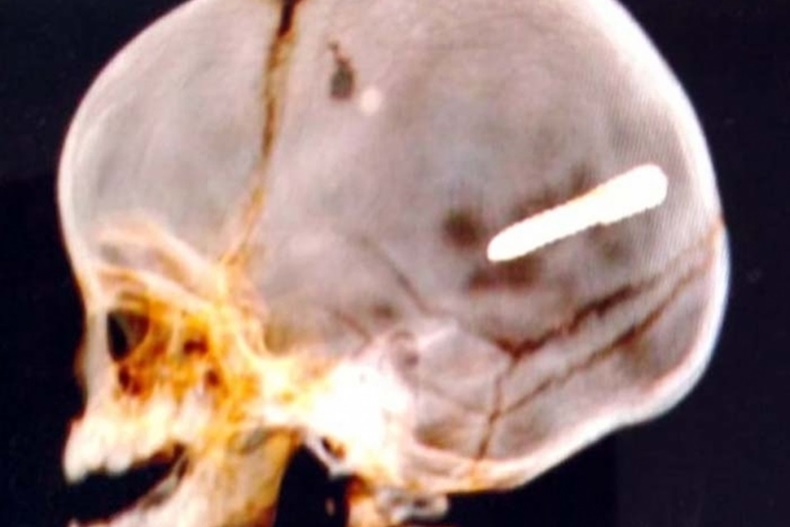

Sentado no colo da mãe e dentro de um carro, um bebê de 10 meses foi atingido por um prego que ficou alojado em seu crânio. O caso ocorreu na noite dessa terça-feira (30/07/2019) no bairro Paciência, localizado na Zona Oeste do Rio de Janeiro. De acordo com a Secretaria Municipal de Saúde, o bebê está em estado grave.

A criança foi transferida depois para o Hospital Pedro II, em Santa Cruz e seu estado seria grave. Um exame de imagem constatou o objeto alojado na cabeça da vítima.

Informações preliminares dão conta de que o prego pode ter partido de pistola usada para fixação de gesso, de uma obra que ocorre nas proximidades onde o carro estava parado. A mulher disse ao O Dia que não tinha ninguém na rua no momento em que o automóvel foi atingido.